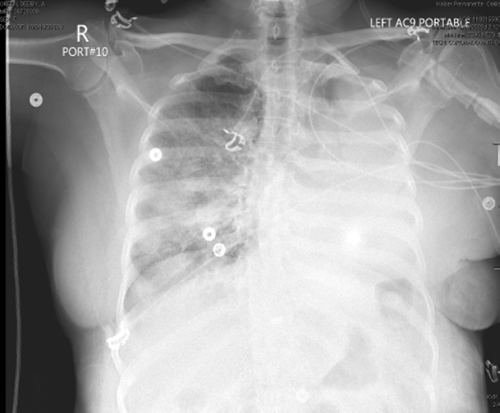

A routine chest X ray on postop day (POD) 1 showed appropriate reinflation of the lung (Figure 1), and the chest tube was removed. She had persistent pain and a brief episode of atrial fibrillation on POD 1-2 and thus remained inpatient for ongoing treatment monitoring. On POD 3, she developed progressively worsening hypoxia with rapid progression, requiring BiPAP with 80% O2 to maintain oxygen saturation >90%. A chest radiograph was obtained, and when compared to the imaging on POD 1, it revealed near whiteout on the left side (Figure 2).

Figure 1. Chest Radiography on POD 1 Following Uncomplicated VATS Left Upper Lobe Lobectomy. Published With Permission